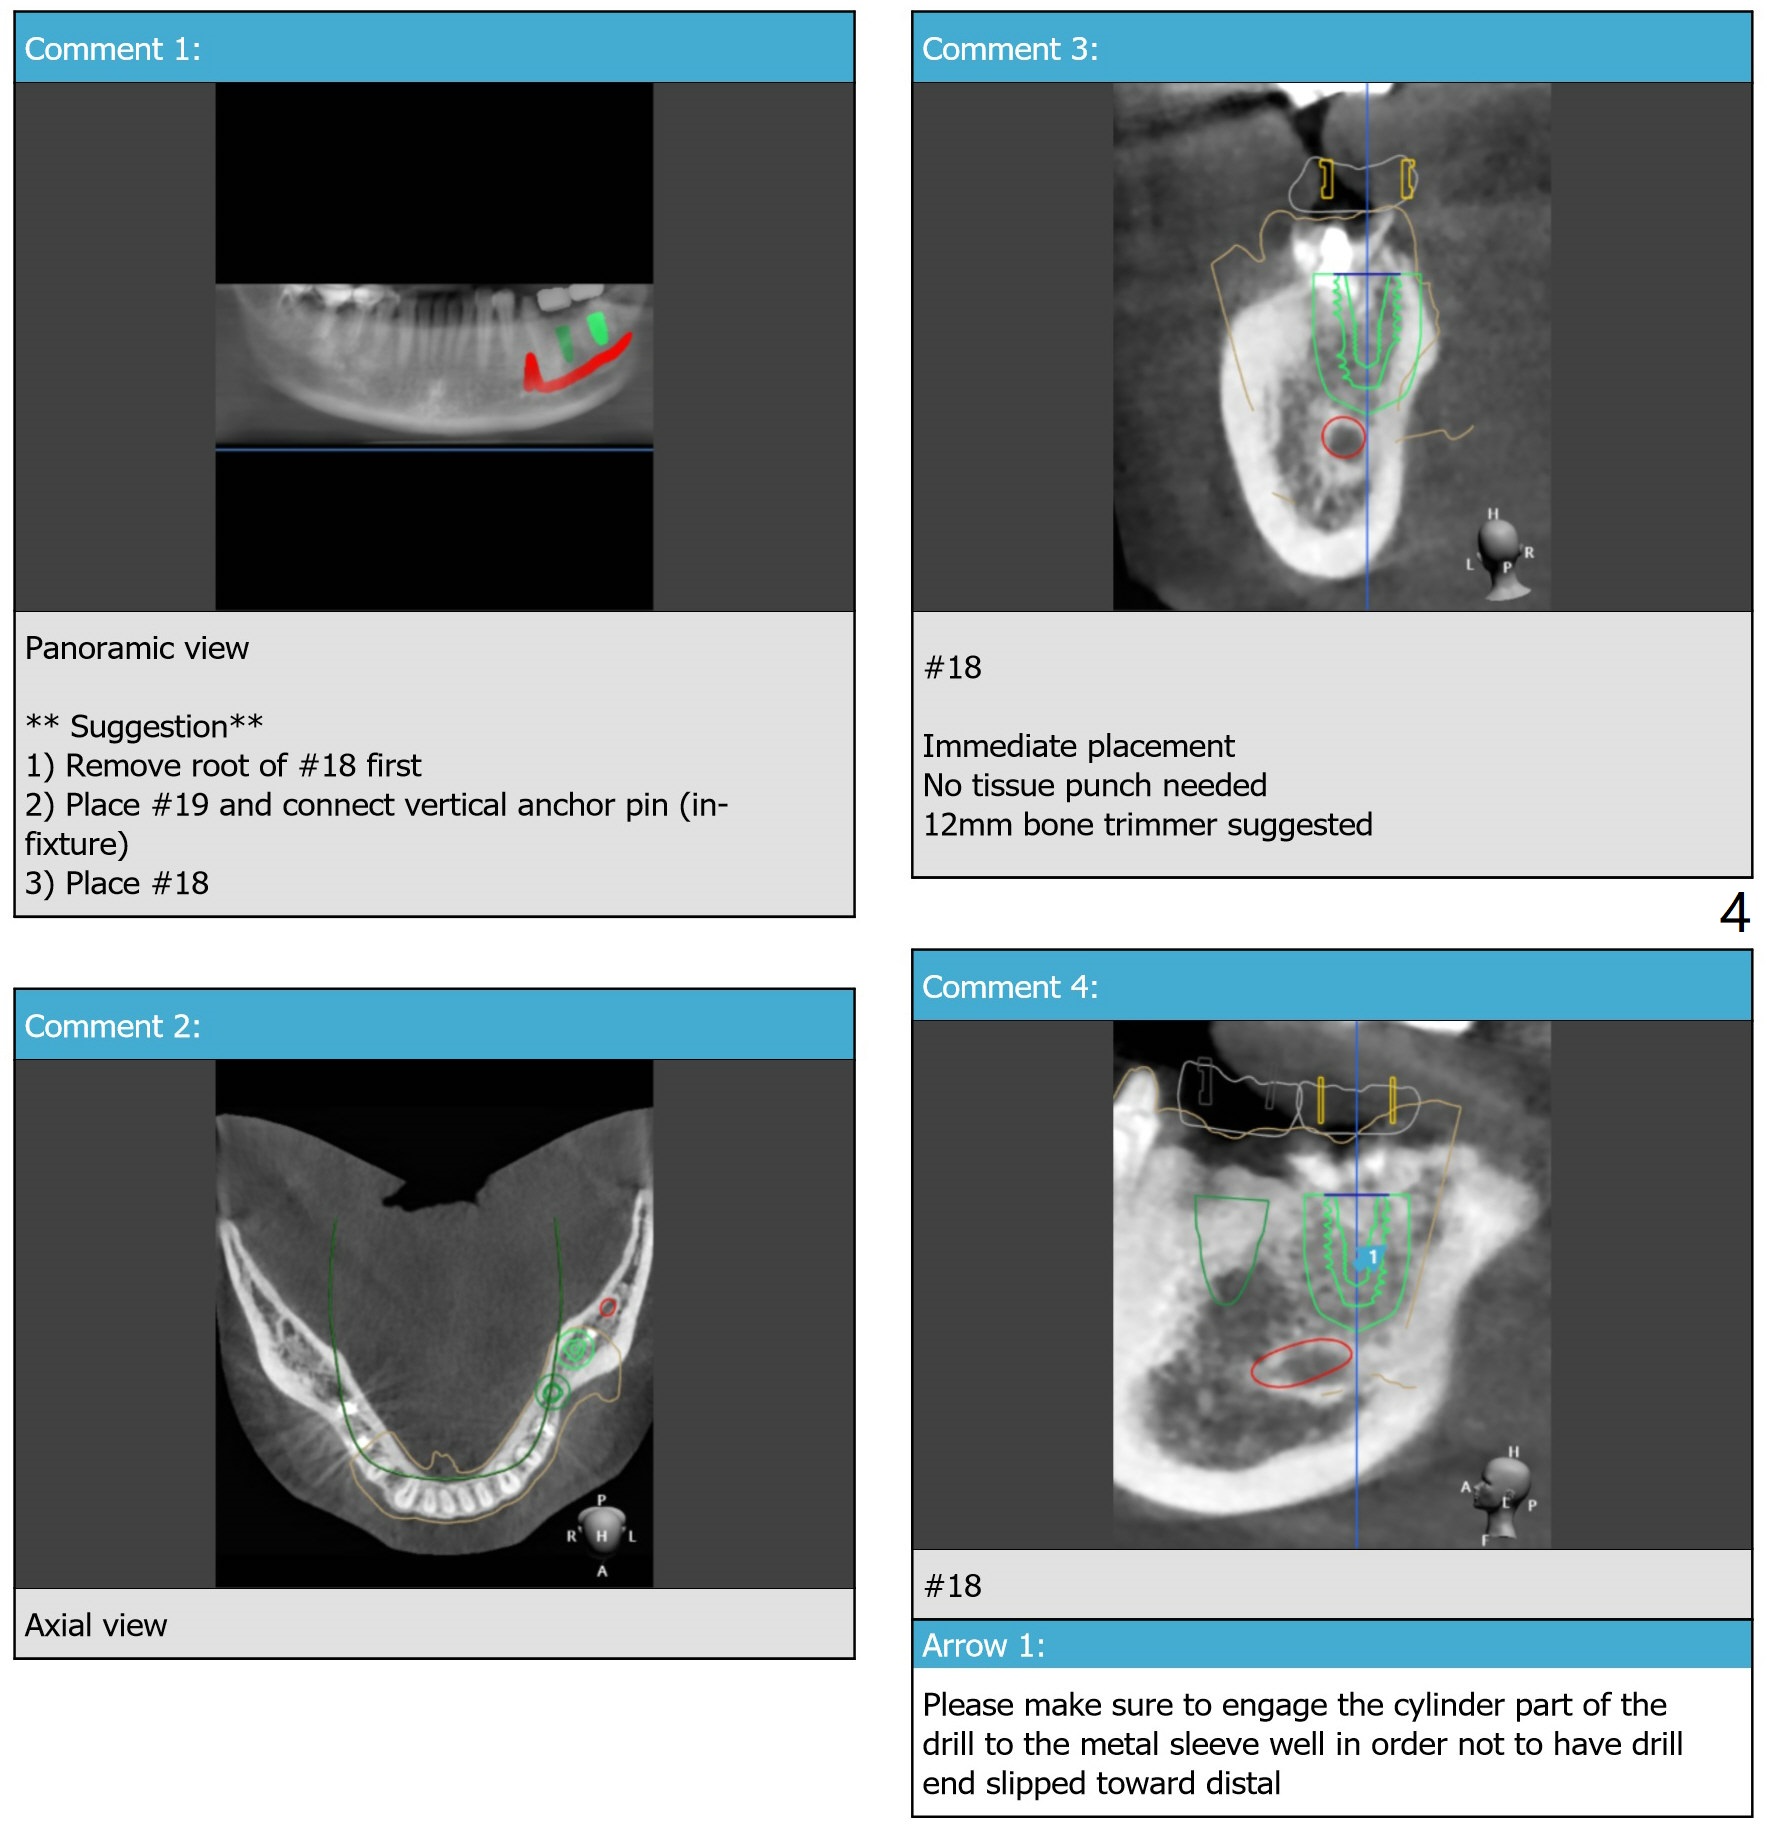

Dense Bone: Overprep

Use IS guide to place IBS implants at #18 and 19 (5x9 and 4x9 mm, respectively), to be consistent with #30. If fixture anchor does not work, use no stop fixture mount. In fact this is true.